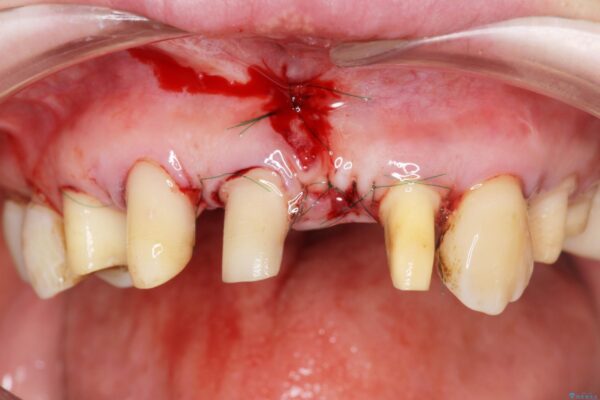

治療中

歯の総合的なマネージメントを行う包括的歯科治療の実践[ 歯周病・矯正・セラミック補綴 ] 治療中画像 歯の総合的なマネージメントを行う包括的歯科治療の実践[ 歯周病・矯正・セラミック補綴 ] 治療中画像 歯の総合的なマネージメントを行う包括的歯科治療の実践[ 歯周病・矯正・セラミック補綴 ] 治療中画像 歯の総合的なマネージメントを行う包括的歯科治療の実践[ 歯周病・矯正・セラミック補綴 ] 治療中画像 歯の総合的なマネージメントを行う包括的歯科治療の実践[ 歯周病・矯正・セラミック補綴 ] 治療中画像 歯の総合的なマネージメントを行う包括的歯科治療の実践[ 歯周病・矯正・セラミック補綴 ] 治療中画像 歯の総合的なマネージメントを行う包括的歯科治療の実践[ 歯周病・矯正・セラミック補綴 ] 治療中画像 歯の総合的なマネージメントを行う包括的歯科治療の実践[ 歯周病・矯正・セラミック補綴 ] 治療中画像 歯の総合的なマネージメントを行う包括的歯科治療の実践[ 歯周病・矯正・セラミック補綴 ] 治療中画像 歯の総合的なマネージメントを行う包括的歯科治療の実践[ 歯周病・矯正・セラミック補綴 ] 治療中画像 歯の総合的なマネージメントを行う包括的歯科治療の実践[ 歯周病・矯正・セラミック補綴 ] 治療中画像